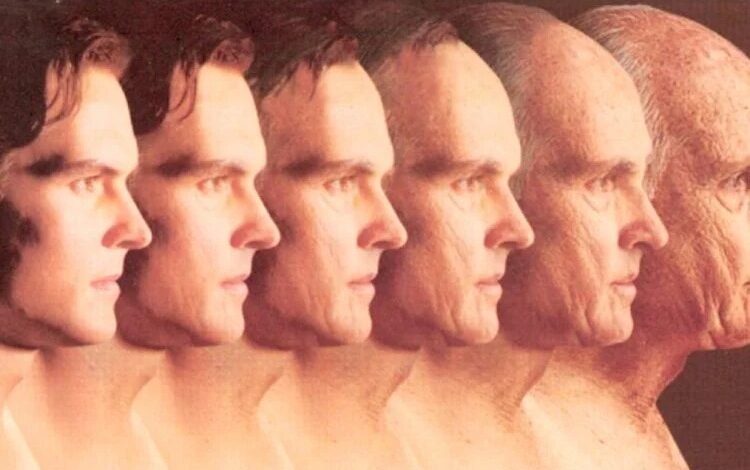

Truri i njerëzve me mbipeshë, 10 vjet më i plakur

Studim: Kafeja mund t’ju ofrojë plakje të shëndetshme

“Epoka e artë” e ilaçeve për humbje peshe mund të bëjë që jetëgjatësia të jetë deri në 100 vite

Shkencëtarët zbulojnë moshën e saktë kur mund të mbetesh obezë përgjithmonë

Truri i njerëzve me mbipeshë, 10 vjet më i plakur